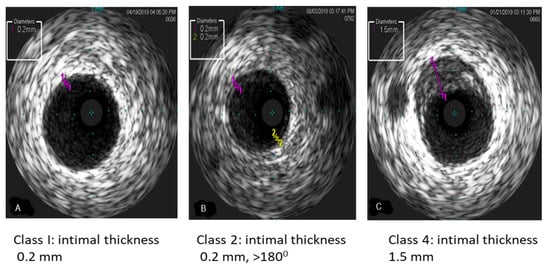

IVUS has been increasingly utilized over the years as it allows for earlier and more accurate detection of early and progressive changes in the coronary vasculature. IVUS has been extensively studied in adults and has emerged as an excellent tool for a more precise quantitative assessment of lumen size and intimal thickening [10]. In adults, the modified Stanford classification [59], based on intimal thickening, has been used for diagnosis and the severity of CAV: Class 1 (minimal) intimal thickness < 0.3 mm and extent of plaque < 180 degrees; Class 2 (mild) intimal thickness < 0.3 and extent of plaque > 180 degrees; Class 3 (moderate) intimal thickness 0.3–1 mm and plaque extent < 180 degrees; and Class 4 (severe) intimal thickness ≥ 1 mm and extent of plaque > 180 degrees. In adults, an intimal thickness of >0.5 mm by IVUS is associated with nonfatal major cardiac events and/or graft loss [60]. Furthermore, more recent data showed prognostic relevance of intimal thickness > 0.35 mm by IVUS within 1 and 5 years of HT [61]. However, IVUS is technically more challenging and is associated with increased procedural risk, including coronary artery spasms and a reported risk of coronary artery dissections in as many as 1.6% of catheterizations [62]. In pediatric HT recipients, IVUS has been limited by patient size and size of available catheters, and IVUS has not shown any correlation with microvascular disease [63]. However, a single-center pediatric study by Kuhn et al. described their experience using IVUS in 30 children seven years or older. The authors concluded that IVUS was more sensitive than angiography in detecting early CAV [64]. Figure 7 describes IVUS findings of early and progressive increase in intimal thickness in pediatric patients after HT. The limitations of IVUS are: optimum imaging protocol is not defined, it is limited to epicardial coronary arteries with sufficient lumen, and no large-scale randomized trial in children is carried out to demonstrate IVUS guided strategy improves outcomes.

Figure 7. The illustration of IVUS shows the progression of CAV. (A) Class 1 (minimal) < 0.3 mm intimal thickening, (B) Class 2 (mild) < 0.3 mm intimal thickness and >180 degrees; and (C) Class 4 (severe) intimal thickness 1.5 mm.